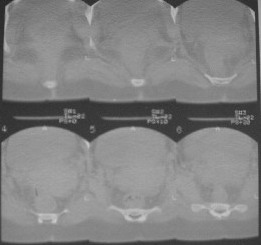

Из анамнеза: в ноябре 2002г. оступилась,упалана трап самолета (на верхней площадке, сразу при выходе из салона) на правый тазобедренный сустав, а затем - вниз на землю на ноги и ягодицы. Потеряла сознание от боли. Доставлена в больницу по месту жительства, лечилась консервативно с диагнозом кокцигодиния.На рентгенограмме от 27.11.02г. вывиха копчика не определяется (снимок идентичен представленной R-грамме от28.11.03г., кроме этого есть нормальная R-грамма копчика в боковой проекции).Через три недели стала ходить, но привести правую ногу в тазобедренном суставе не могла. Сейчас ходит отведя кнаружи правое бедро и голень, как ножку циркуля (фото 1). Неврологических нарушений нет. По просьбе врачаможет на 30-40 секунд поставить ноги вместе (фото 2). При этом испытывает сильную тянущую боль и ощущение "вывернутости" в правом тазобедренном суставе. Эти ощущения заставляют вновь отвести бедро. В положении лежа разогнуть бедро полностью не может из-за болей в ягодичной мышце (фото 3). Сгибание также ограничено из-за болей (фото 4). Отведение в положении лежа возможно в том же объеме, что и стоя (фото 5). Заподозрен старый разрыв правого крестцово-подвздошного сочленения.Выполнено R-исследование и КТ(в приложении). По-поводу деформации лонного сочленения выяснен гинекологический анамнез. Роды одни, нормальные в 22 года. Из роддома выписана на 8 сутки, нарушения походки не было, R-графия таза не проводилась. Вопросы на обсуждение: 1. Диагноз либо алгоритм дальнейшего обследования. 2. Лечебная тактика (в первую очередь возможность и целесообразность оперативного лечения).

Уважаемый Юрий Алексеевич, сделаны ли пациентке более дистальные срезы КТ с захватом области тазобедренного сустава? Учитывая давность травмы, могли присоединиться и дистрофические процессы в субхондральной кости головки и впадины. Изменения в капсуле будут хорошо видны на УЗИ, особенно в сравнении со здоровой стороной. Эффективность лечебно-диагностического введения гормональных препаратов, на мой взгляд, сомнительна ввиду давности патологического состояния. При такой стойкой и давней контрактуре без операции вряд ли можно обойтись. Под наркозом амплитуда на разгибание должна увеличиться, усилить эффект можно тено-миотомиями заинтересованных групп мышц, капсулотомией + в послеоперационном периоде хорошее консервативное противовоспатлительное лечение с укладками на разгибание.Что мешает приведению пока не ясно, во встретившихся в нашей работе аналогичных ситуациях причиной был формирующийся медиальный остеофит головки, выталкивающий её из впадины.